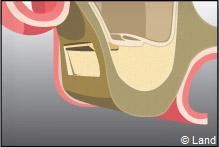

Une fenêtre est délimitée et réclinée à l’intérieur du sinus de manière à aménager un espace. Cet espace est rempli par le matériau de comblement qui peut être recouvert par une membrane.

L’implant est posé dans la même séance ou 4 à 6 mois après la chirurgie de comblement.

Après le comblement, il n’a jamais été décrit une quelconque perturbation de la physiologie sinusienne.